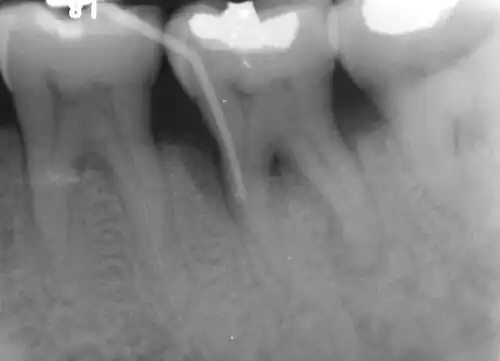

Diagnosis

Nabers probe is used to check for furcation involvement clinically. Recently, cone beam computerised technology (CBCT) has also be used to detect furcation.[5] Periapical and interproximal intraoral radiographs can help diagnosing and locating the furcation.

Only multirooted teeth have furcation. Therefore, upper first premolar, maxillary and mandibular molars may be involved. Upper premolars have one buccal and one palatal root. Maxillary molars have three roots, a mesio-buccal root, disto-buccal root and a palatal root. Mandibular molars have one mesial and one distal root, and so.